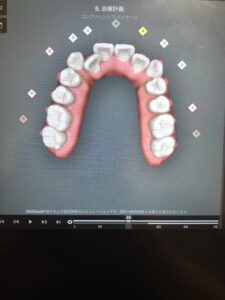

30枚目になると、ようやく正面からでも変化がわかるようになりました。

今回はアライナー10枚ごとの歯の動きを見ていただきましたが、実際は1枚ずつ歯の動きをご覧いただけます。

どのように歯を動かしてどんな歯並びになるのかを患者様と一緒に見ることができるので、自分の理想の歯並びになるのか確認していただいた上で矯正治療を始めることができます。